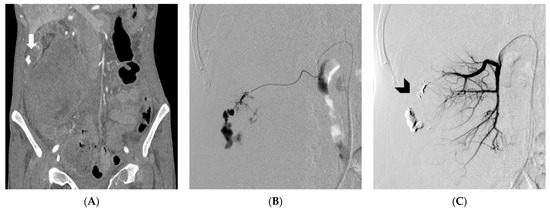

- Tiralongo, F.; Seminatore, S.; Di Pietro, S.; Distefano, G.; Galioto, F.; Vacirca, F.; Giurazza, F.; Palmucci, S.; Venturini, M.; Scaglione, M.; et al. Spontaneous Retroperitoneal Hematoma Treated with Percutaneous Transarterial Embolization in COVID-19 Era: Diagnostic Findings and Procedural Outcome. Tomography 2022, 8, 1228–1240. [Google Scholar] [CrossRef]

- López-Martínez, L.; Molina-Nuevo, J.D.; Pedrosa-Jiménez, M.J.; Juliá-Mollá, E. Spontaneous Haematomas in Anticoagulated COVID-19 Patients: Diagnosis and Treatment by Embolization. Cardiovasc. Interv. Radiol. 2022, 45, 1001–1006. [Google Scholar] [CrossRef]

- Ierardi, A.M.; Xhepa, G.; Duka, E.; Laganà, D.; Ianniello, A.; Floridi, C.; Bacuzzi, A.; Reginelli, A.; Squillaci, E.; Brunese, L.; et al. Ethylene-vinyl alcohol polymer trans-arterial embolization in emergency peripheral active bleeding: Initial experience. Int. Angiol. 2015, 34, 28–35. [Google Scholar]